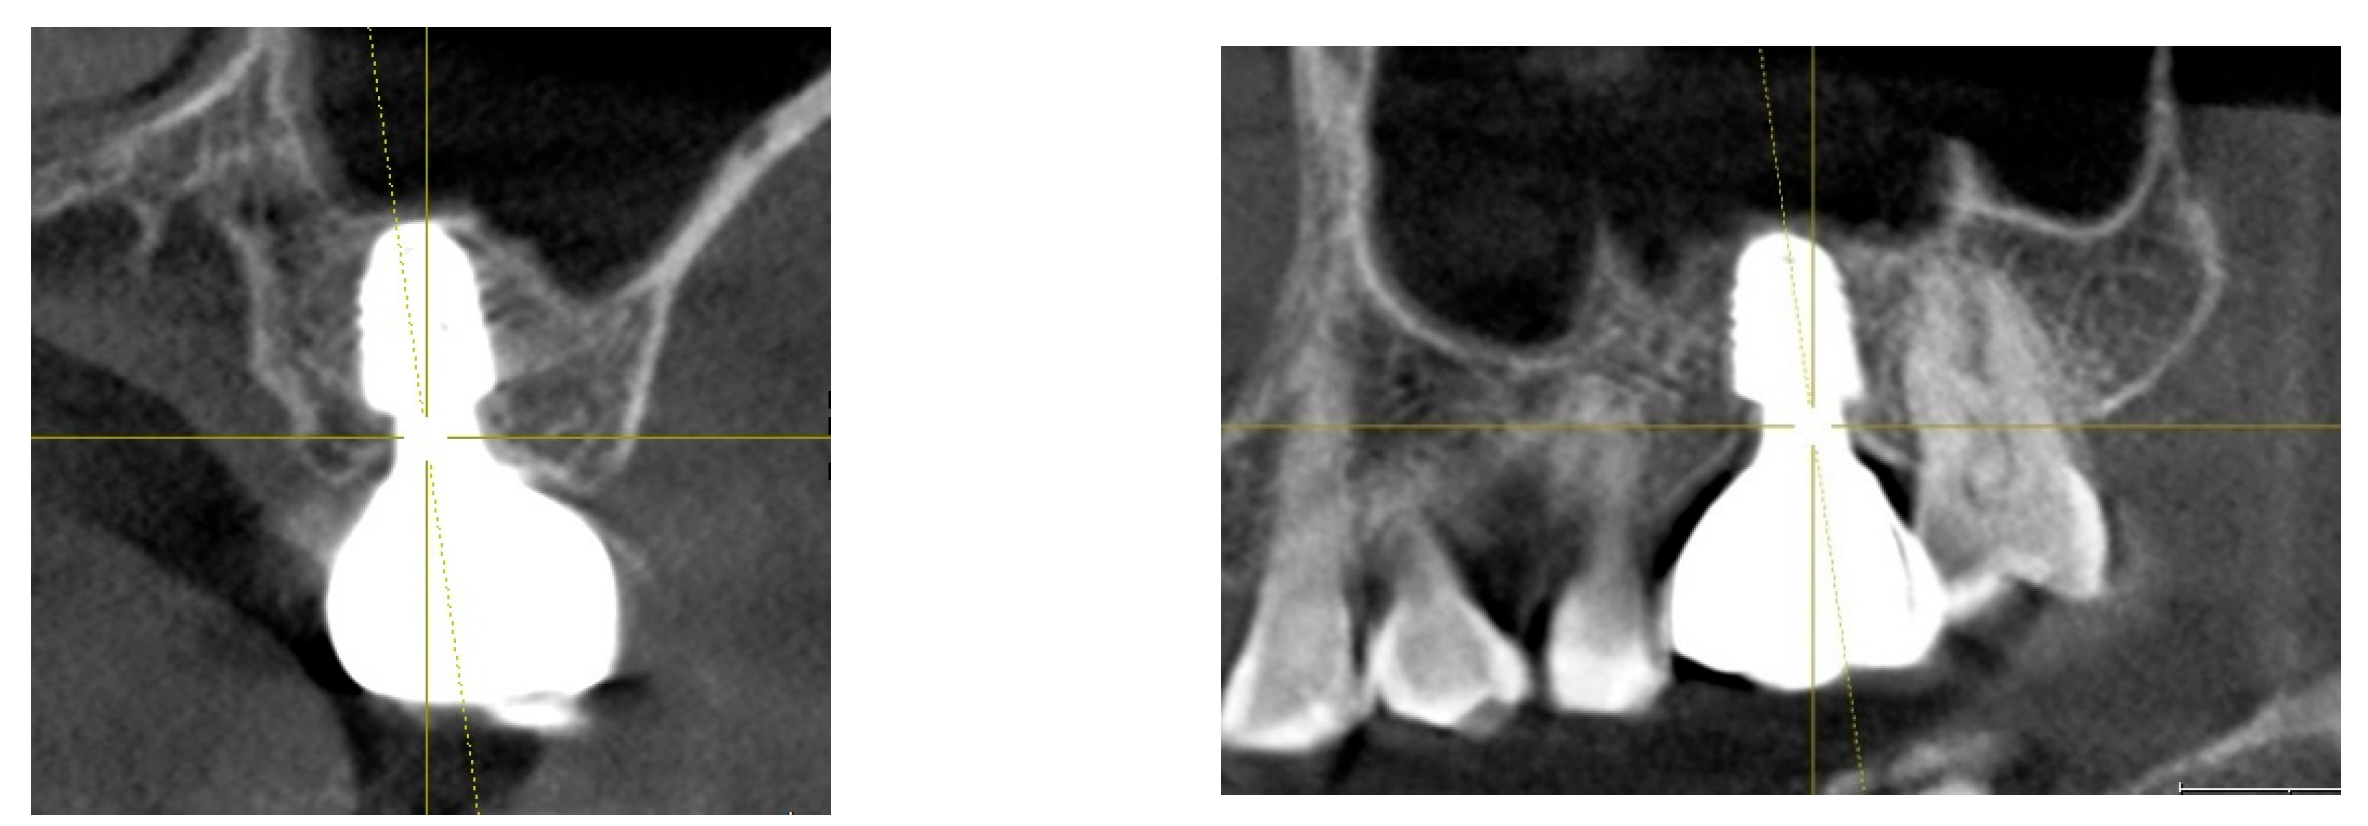

Several studies have demonstrated that subcrestally placed implants provide stable peri-implant conditions and minimize crestal bone loss over time. (Figure 1) Bicon implants, widely used during the 2000s and 2010s, were often placed subcrestally, leading to lasting biological stability [24]. SPIs are commonly used in cases with narrow or sloped ridges, where deeper placement ensures that the implant’s rough surface is fully embedded in bone. This approach is also beneficial for achieving a natural emergence profile, especially in molar regions. Despite their clinical success, SPI outcomes in the literature have been inconsistent, possibly due to:

Figure 1. Results after 10 years of subcrestally placed implants (SPI) – Fixtures were placed subcrestally, with X-rays showing no crestal bone loss and clinical photos demonstrating healthy peri-implant soft tissue and a natural emergence profile. This approach reflects a trend seen with Bicon implants during the 2000s to 2010s, where implant fixtures were often placed slightly deeper than those of other systems to support lasting stability.